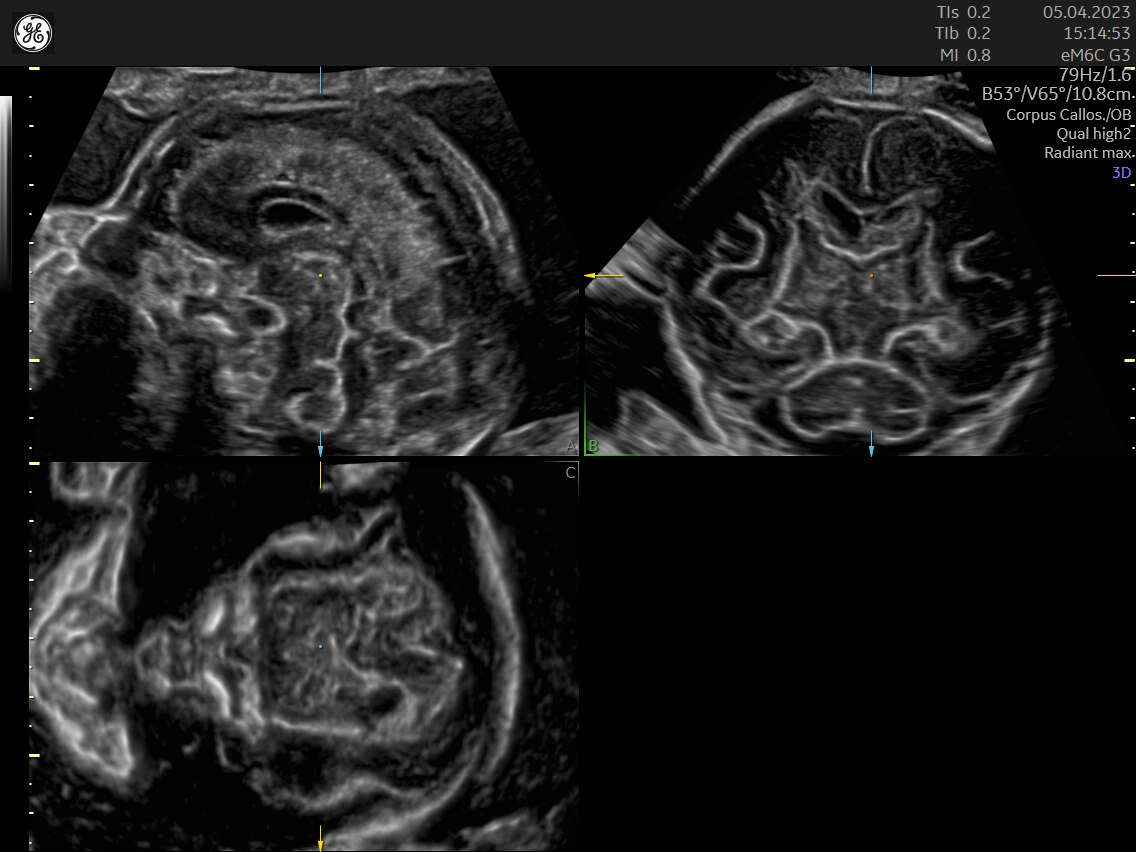

Fetal Heart Assessment

Detect, diagnose, and monitor with confidence using Radiant and fetal HQ

FETAL HEART EVALUATION

Get to the Heart of the Matter

Identifying fetal cardiac abnormalities earlier means you can intervene sooner, plan for delivery, and potentially improve outcomes. The Voluson Expert 22 provides a full solution of progressive tools, to help distinguish the tiniest structures with stunning clarity to provide patient answers faster.